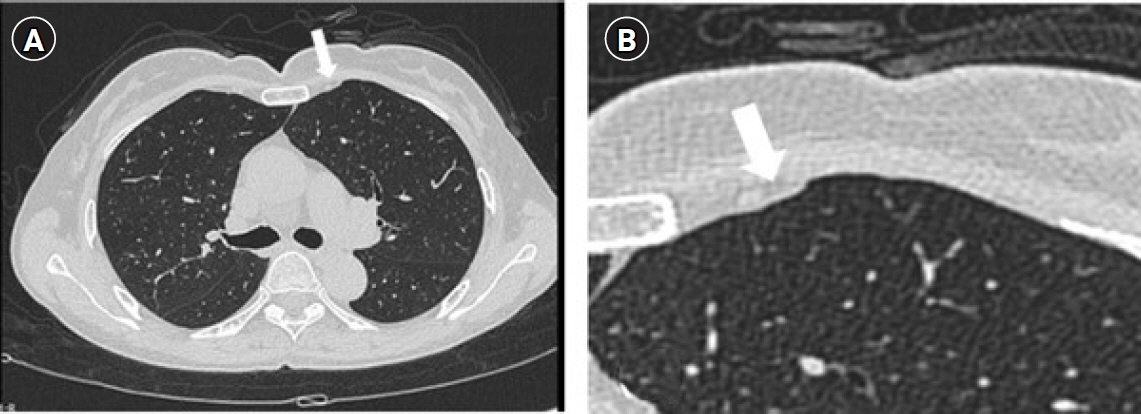

Pleurisy is an inflammation of the parietal pleura and is characterized by pleuritic pain. The most common cause of pleurisy is infection; other causes include rheumatoidarthritis, malignancy, rib fractures, or trauma. Possible causes of chest pain associated withgolf include costochondritis, stress fractures of the ribs, intercostal muscle strain, or, rarely,Tietze’s syndrome and slipping rib syndrome.Case: A 64-year-old female presented with intractable chest pain that began 4 months priorwhile playing golf. No specific cause was found after various examinations. There was persistent pain despite medical treatment. Ultrasonography (US) was performed over the painful areas, which revealed focal pleural effusions. A mixture of ropivacaine and triamcinolonewas injected into the focal pleural effusions using US guidance, which dramatically relievedher pain.Conclusions: This case demonstrates that US can be used as a diagnostic and therapeuticmodality for intractable chest pain with an undetected pathology.